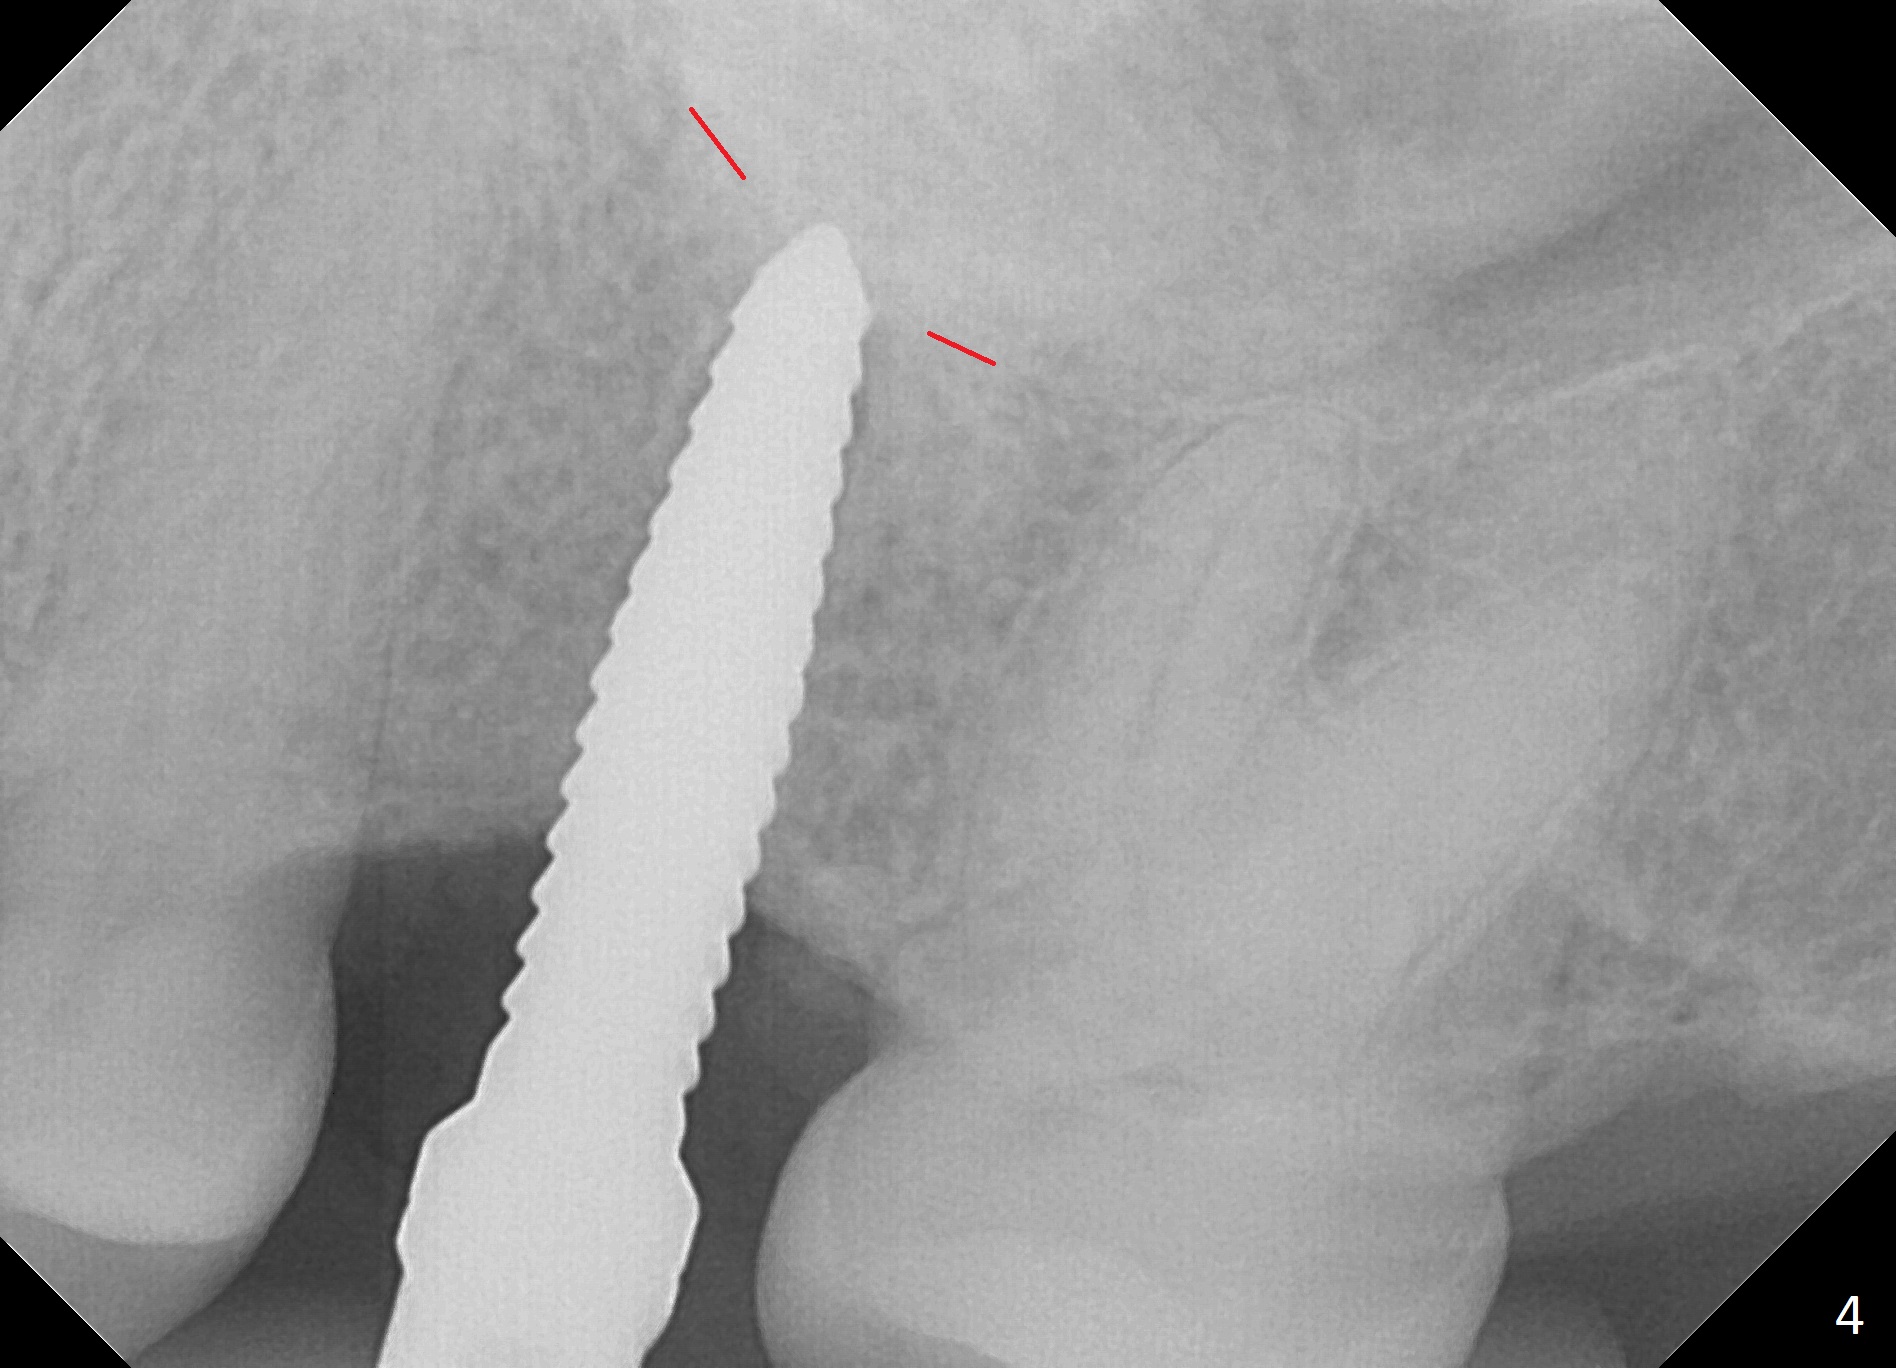

The edentulous area at #14 is moderately atrophic, After incision, the bone is too hard for #15 blade for bone expansion. Osteotomy is initiated with 1.2 mm drill, followed by insertion 1.3/2.3 mm bone expander (Fig.1). Use the same instruments are reused twice to change the trajectory (Fig.2,3). Finally Lindamann bur is utilized to move the osteotomy distally by ~ 2 mm; bone expansion continues until 2.4/3.7 mm expander for 13 mm with 50 Ncm (Fig.4). The last expander 3/4.4 mm barely enters the osteotomy for 6 mm. A 3.7 mm drill has to be used for 12 mm before placement of a 4.5x11.5 mm implant with >35 Ncm (Fig.5). A 5.5x5(3) mm abutment is placed with allograft (<) placed around the implant. Following suturing, periodontal dressing is applied around the implant. The abutment dislodges 3 months postop (Fig.6). Crown is delivered 3 weeks later. The abutment screw is retightened ~ 2 months later. He is a bruxer. The abutment screw is loose again <2 years post cementation (6 months post #18 screw retightenting and occlusal reduction), probably related to distal implant placement (Fig.7).